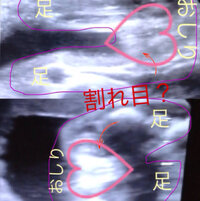

赤ちゃんの性別判定 現在妊娠8ヶ月の妊婦です! 私の通ってる病院は初期から聞いてもないのに積極的に性別を教えてくれる病院で(^^;) 17週頃にちょうど赤ちゃんの小股部分がチラっと映った時に、突起物!?のようなものが出てるから男の子かも! 縦と横方向からだけではなく、色々な方向から赤ちゃんが見えるようになるため、早い人ではこの頃に性別を産婦人科の先生から知らされます。 しかし女の子は以下に引用するように、5ヶ月ではまだわからないことが多いです。 女の子は男の子特有のシンボルが足の間にはなく、外陰部らへんに女性の大陰唇と分かる割れ目が見えると女の子です。 こちらはよ~く見てみないと分か

医師が性別を判断する決めては、男女それぞれの外性器です。 XXの染色体をもつ女の子の未分化性線は子宮や膣、XYの染色体をもつ男の子の未分化性線は精巣や陰嚢、陰茎を作ります。 しかし、妊娠初期の段階では胎児が小さすぎるため、エコー検査では判別ができません。 妊娠7~8週目くらいで性の分化が始まって男女の性器が作られ始め、 11~12週目になって、男の子には男性Q赤ちゃんの性別 現在妊娠5ヶ月です。 赤ちゃんの性別が早ければ次の健診でわかるかなーとどきどきしていますが、皆さんはいつ頃わかりましたか? 一度言われた性別が訂正されることもあるようなので確定ではないと思いますが、わかった時期や性別 うちの義母は女の子希望です。 息子の時に男の子だったと言ったら 手で顔を覆い 赤ちゃんの性別が判明した時期は、6~7ヶ月頃が約半数 6~7ヶ月頃が最も多く、約半数(51%)でした。4~5ヶ月頃が28%、8~9ヶ月頃が14%となりました。